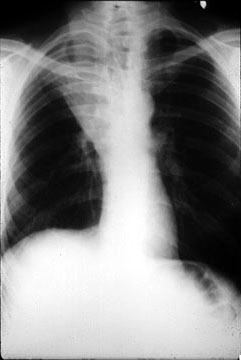

Most bronchogenic carcinomas form a mass in or near the

hilus. Some neoplasms, especially the adenocarcinomas, form a mass in the periphery of

the lung. Refer to Figure 15-42 in your textbook. The following classification scheme